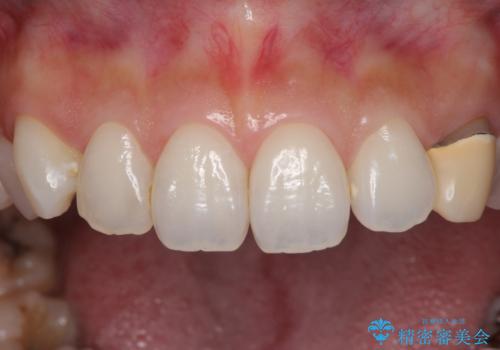

- 前歯の保険のかぶせものをセラミックに替えたいと来院された患者様です。

保険のかぶせもの特有の変色や縁の金属色、歯根が一部見えている点が気になるとのことでした。

土台の金属を除去してファイバーコアによる土台植立を行い、オールセラミッククラウンにて補綴することとしました。